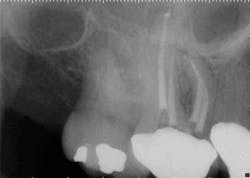

maxillary central incisor with a necrotic pulp. A prominent lateral canal can be seen,

but there is no way to know if multiple microscopic branches are present at any level

of the root canal system.